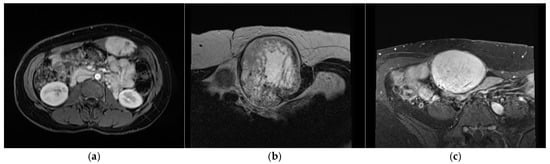

2.2. Procedure and Technique